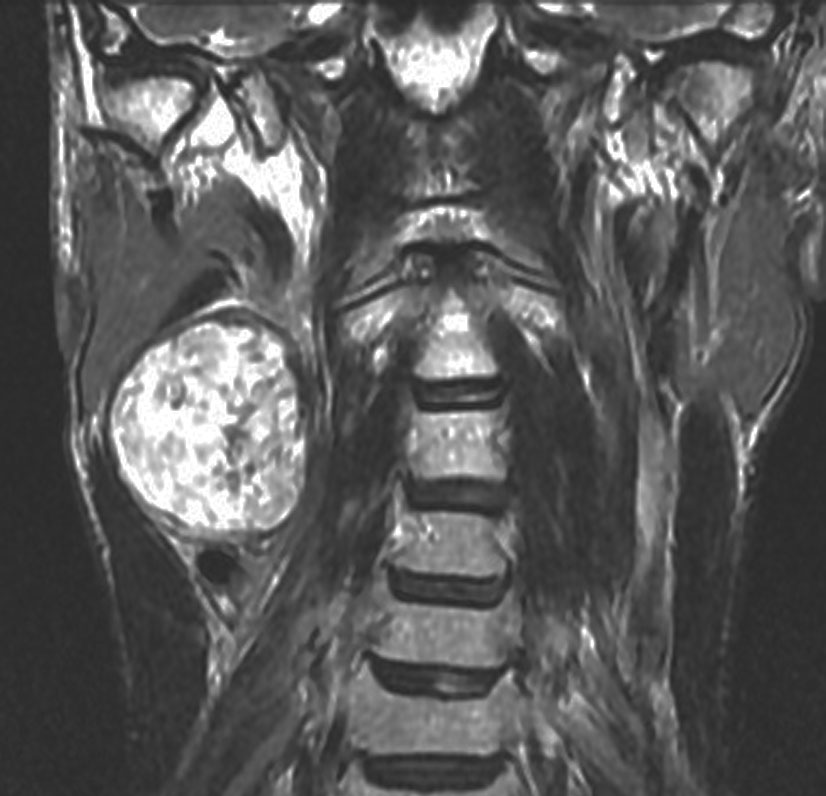

症例:頸静脈孔より下の深頸部のもの:副咽頭間隙腫瘍

左頸静脈孔の下の迷走神経節から発生したものです。ごく軽い飲み込み辛さだけが症状でした。

内頚動脈を強く圧排して,外形動脈からはかなり豊富な血流が流入しています。頭頸部外科で顎骨を割るような手術を計画されていました。

でも,右側の画像で見るような角度から,小さな頸部の皮膚切開だけで,胸鎖乳突筋だけを乳様突起から外して翻展して摘出できました。内部からほじくるように摘出すれば症状悪化はないのですが,周囲軟部組織から切断して剥離しようとすると厳しい嚥下障害と嗄声になります。

手術で全摘出しましたが嚥下障害などはでませんでした。普通のおとなしい神経鞘腫ですから再発はありません。